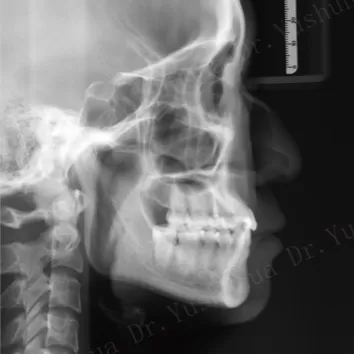

X-rays before treatment

[Panoramic Radiography/Lateral Cephalogram]